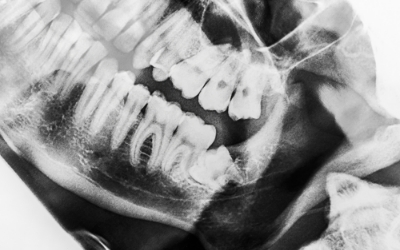

説明には、目で見て理解できる資料を使います。レントゲン写真はもちろん、症例によっては歯科用CTでお口の状態の立体図をお見せすることもあります。まずはご自身の現状を把握していただければと思います。当院は、そのうえで患者様が選ばれた治療を尊重します。